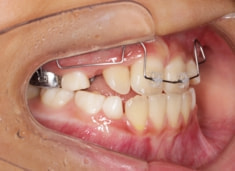

検査時のレントゲン分析では、上下顎の関係は、上顎の劣成長があり下顎前突傾向という値がでておりましたが、前歯ジャンプ後はフェイスマスクの効果もあり、上下顎の関係は正常化しています。

上顎が若干優位になっていますので、今後の下顎の成長のための貯金になっているくらいです。